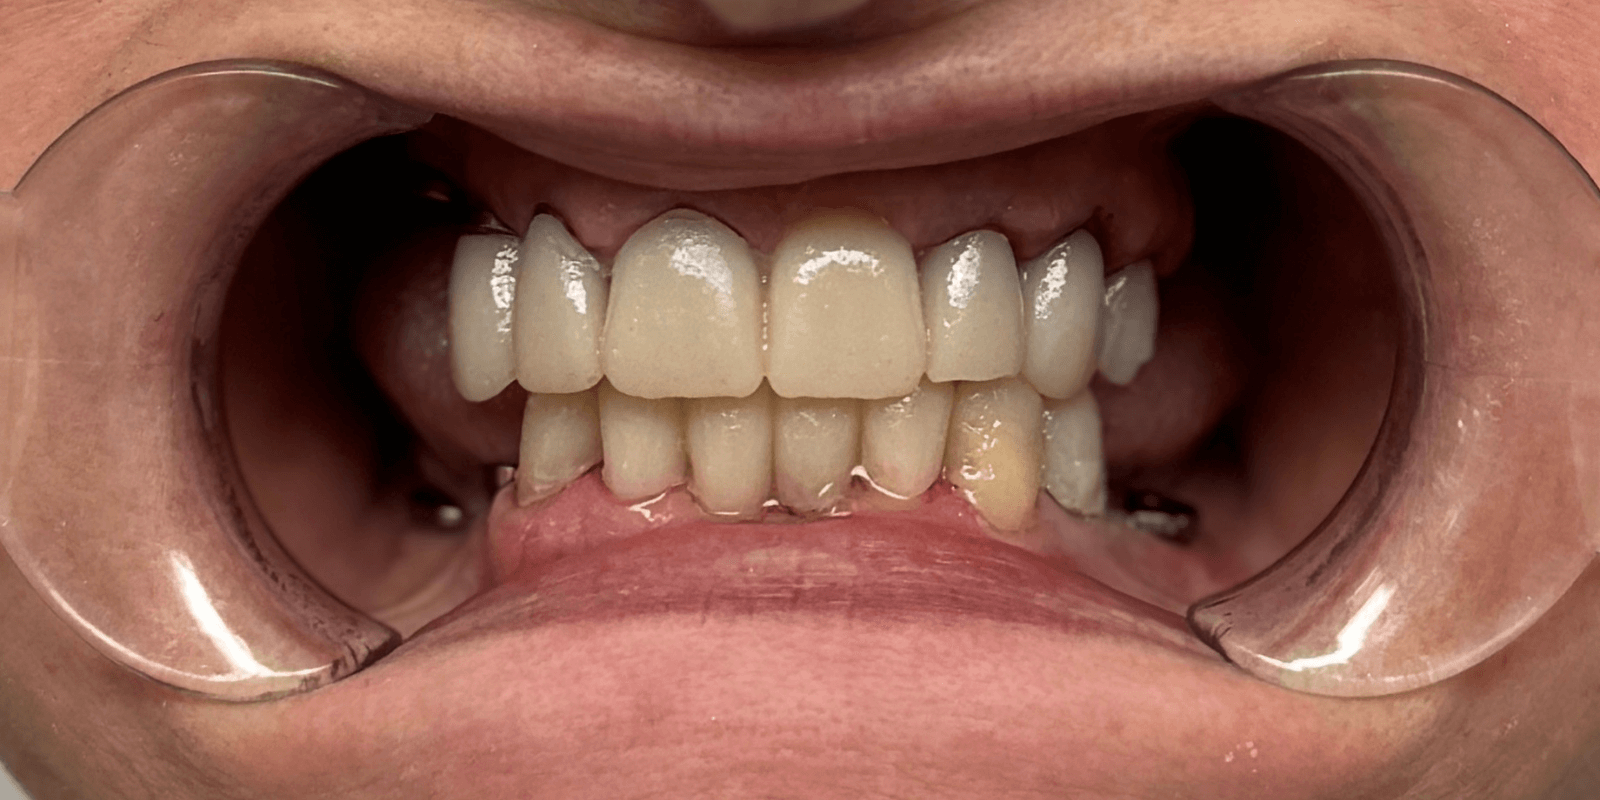

- Ортопедические конструкции изготовить из диоксида циркония, цвет bleach-2.

Итог

С момента первого визита прошло чуть менее трех месяцев. И когда пациентка в последний раз посмотрела в зеркало – мы увидели не просто улыбку. Мы увидели, как человек словно вернулся к себе.

Ее глаза засияли. Плечи расправились. Она начала смеяться громче. Ее жизнь изменилась не потому, что появились новые зубы, а потому, что исчезли все комплексы, которые годами мешали жить свободно.